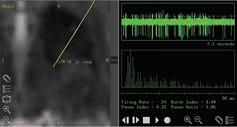

Left: The stereotactic headframe and intraoperative CT scan

Right: An example of the brain activity recorded during a DBS procedure

In essence, DBS works by jolting the brain’s malfunctioning electrical currents back into their natural rhythm through a wristwatch-sized device called a neurostimulator. A neurosurgeon threads a small wire with an electrode at the end through an opening in the patient’s skull until the electrode reaches the target spot. That wire and electrode are then connected, via another small extension wire, to the neurostimulator, which is implanted just under the patient’s skin near his collarbone. In the weeks and months after the surgery, a programming expert finely calibrates the neurostimulator’s settings, such as amplitude and frequency, to deliver just the right “dose” of electrical impulse.

GETTING INTO A RHYTHM